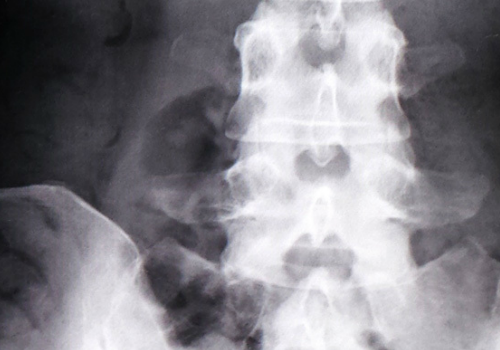

腰痛をはじめヘルニアなどでのマットレスの対策には何が必要か?

昔よく言われていた、堅いマットレスはヘルニアに良いのか?

など、ヘルニアの方がマットレスを探す際の注意点などを含め、解説していきます。